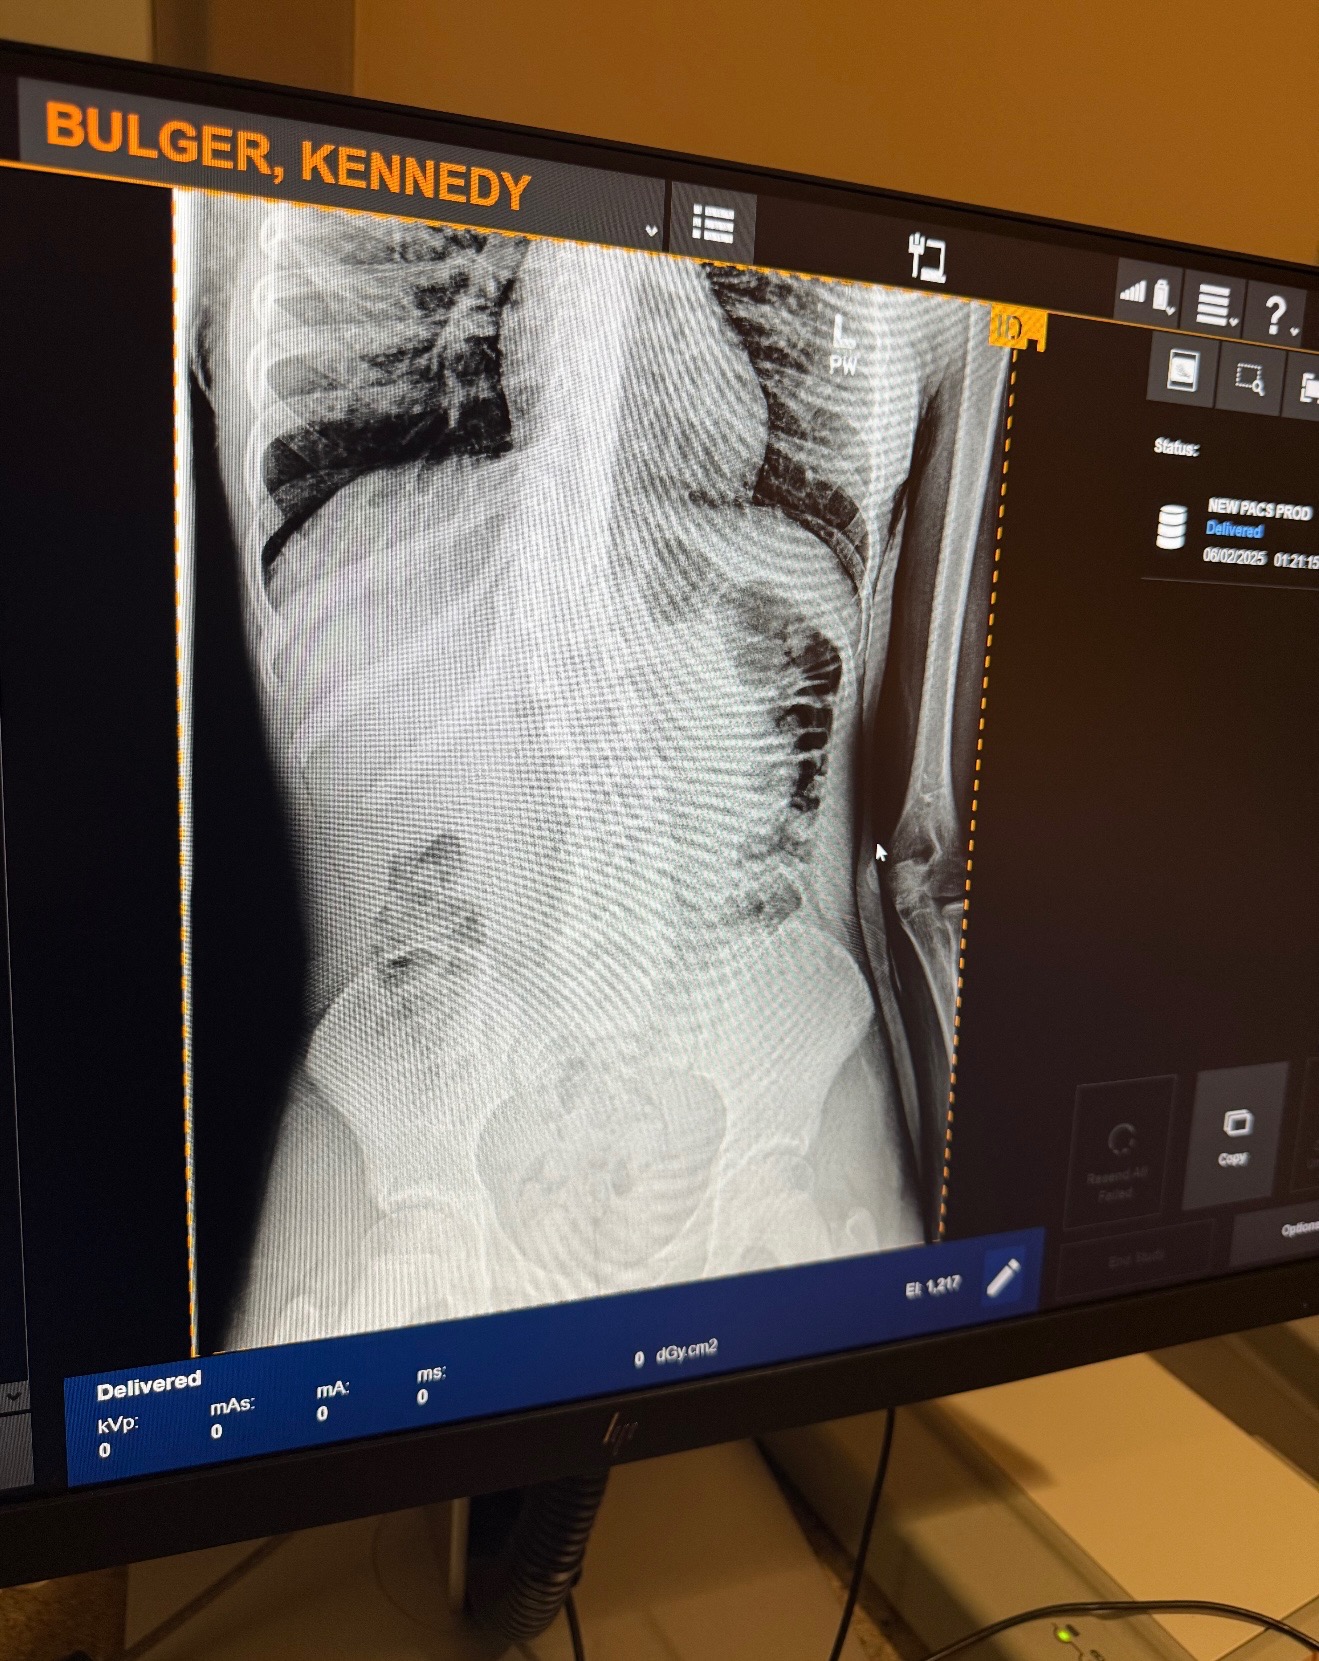

About a year ago, my family and I found out that I have a mild case of scoliosis, which means my spine is curved in a way that causes pain, fatigue, and difficulty moving around like other kids my age. My doctors say that if we act now, I can avoid surgery, but only if I wear a special custom-made medical back brace every day to help straighten my spine as I grow. Time is critical. I am currently only 5 degrees from my scoliosis progressing from mild to moderate. The longer we wait, the more my spine will curve, making it harder to treat and putting my health at greater risk.